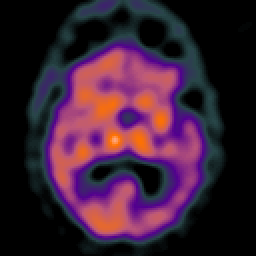

Subdural Hygroma,overlay -- Slice #24